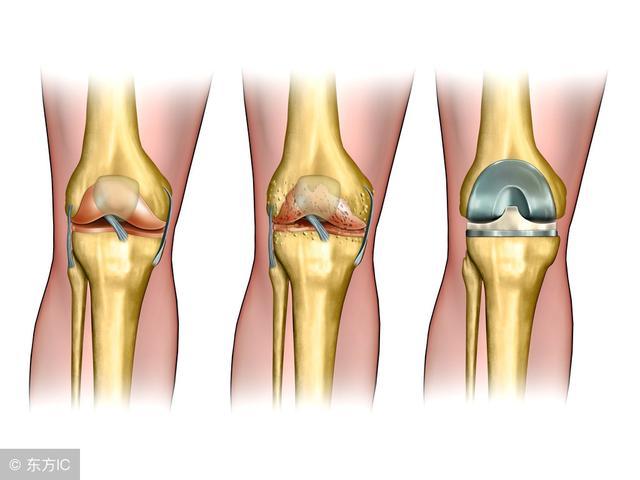

16、骨关节炎

常见(>50岁)

膝关节痛

早期:活动开始时痛、剧院征、上下楼梯时痛、下蹲起立时痛,休息能缓解;

中后期:负重痛、行走痛、夜间痛

短时晨僵 (<20分钟),活动后消失

可有滑膜炎急性发作,关节间隙压痛,活动度减少

关节摩擦音,轻~中度关节积液

X线摄片:负重位前后位、侧位和髌股关节切线位。